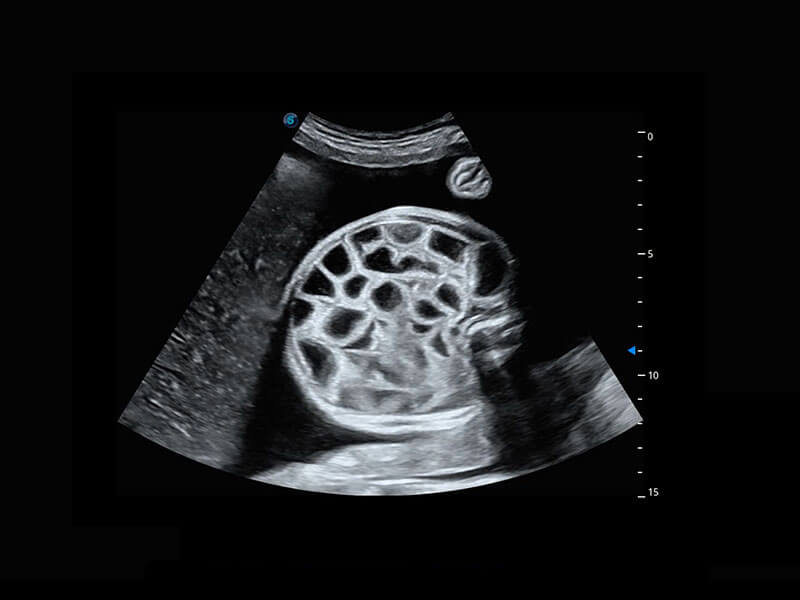

腔内三维-宫内节育器

P60优异的图像质量搭载专科探头,在妇科基础疾病的诊断、卵泡生长的监测、输卵管通畅情况的判别等方面为您提供生殖应用方案。